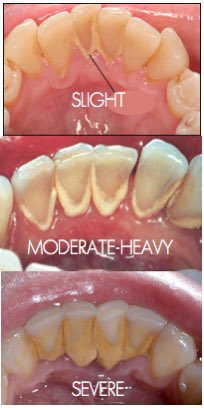

Sekiranya anda menghidap diabetes badan termasuklah mulut tidak cukup kuat untuk melawan jangkitan. Gusi menurun sehingga gigi nampak panjang dan lain-lain lagi Banyak faktor-faktor yang meningkatkan risiko penyakit gusi di kalangan orang dewasa seperti. Plak yang menumpuk dapat menyebabkan gingivitis atau radang gusi.

Dengan begitu risiko gusi berdarah akibat bulu sikat yang terlalu keras bisa berkurang. Di bawah kami senaraikan 6 punca mengapa mulut anda kerap berdarah ketika menggosok gigi. Di Malaysia kajian telah menunjukkan bahawa kehadiran tartar adalah sebagai kekerapan tertinggi 414 pada semua keadaan gusi di kalangan dewasa Malaysia NOHSA 2010.

Berikut ini adalah beberapa tips yang dapat Anda lakukan untuk mencegah gusi sering. Hasilnya wujud masalah gingivitis. Gusi berdarah umumnya terjadi akibat penumpukan plak di garis batas gigi dan gusi.

Penyebab Gusi Berdarah. Plak merujuk kepada sebarang lebihan makanan mukus atau. Apabila tidak ditangani plak dapat mengeras menjadi karang gigi dan berisiko menyebabkan gusi berdarah.